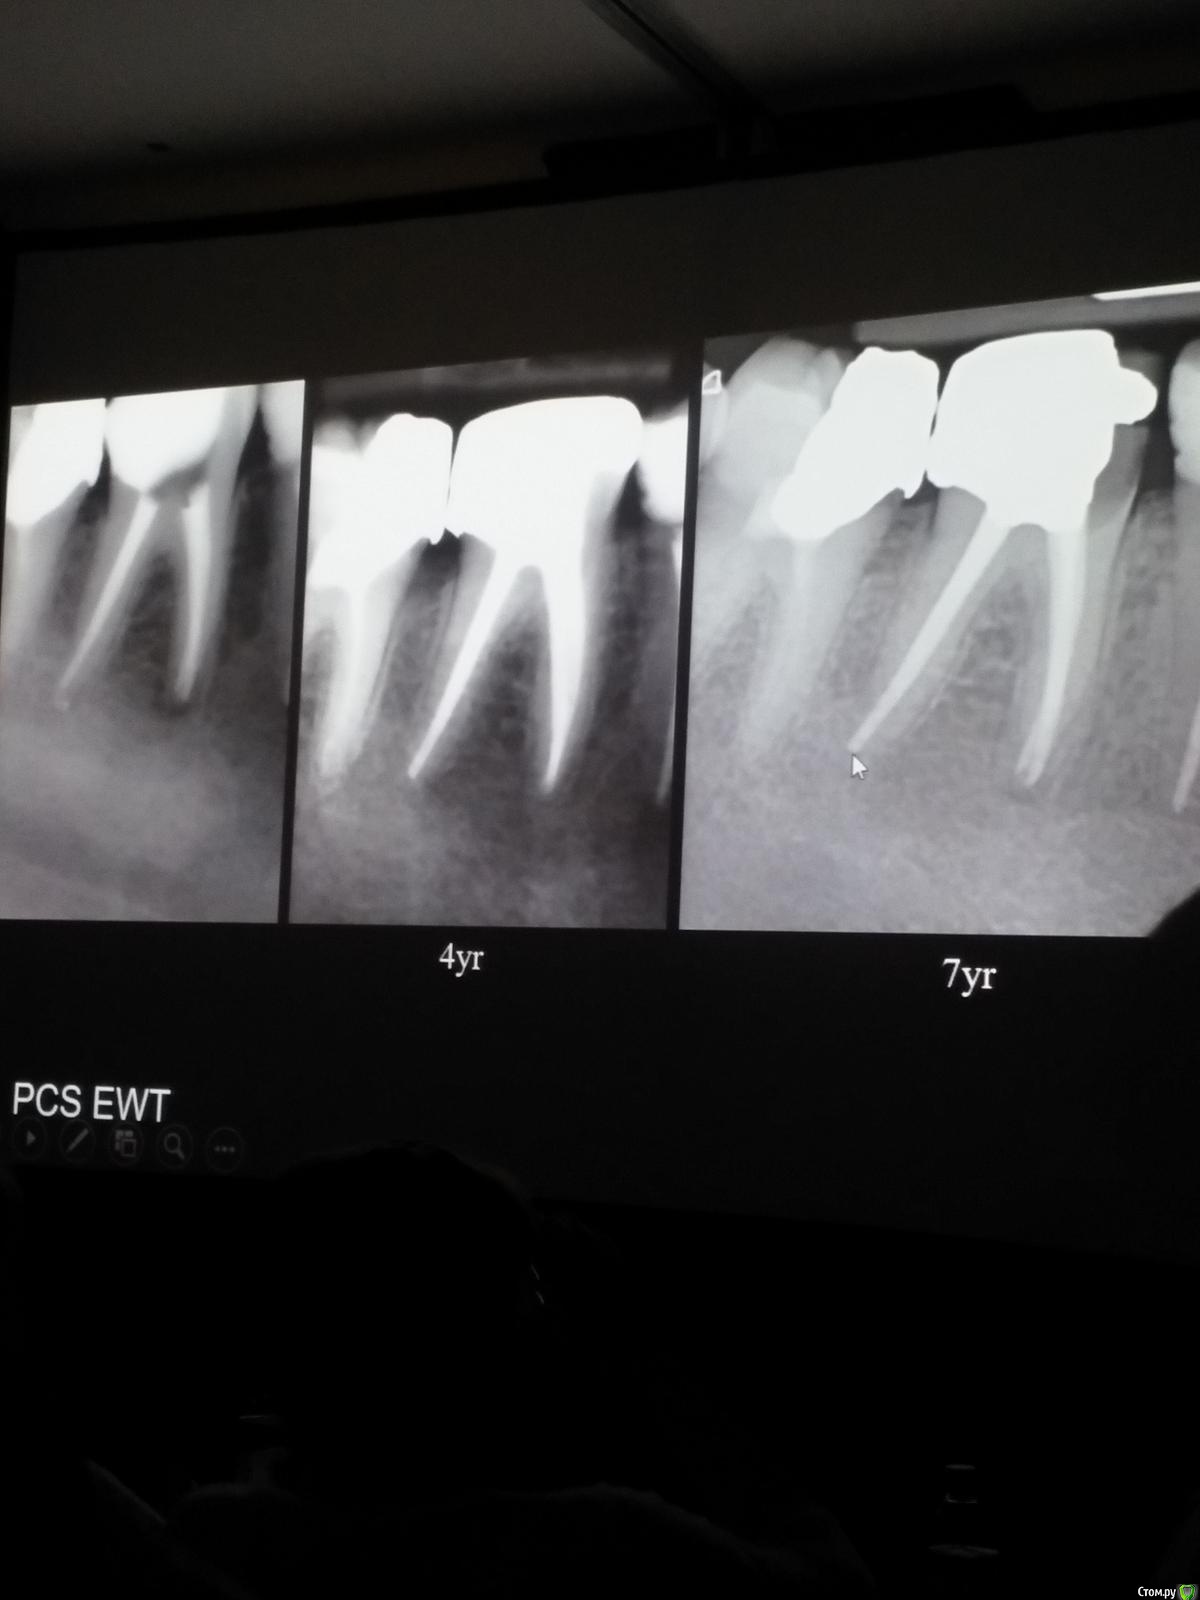

Популярный пост Kolchanov Опубликовано 11 марта, 2017 Популярный пост Поделиться Опубликовано 11 марта, 2017 (изменено) Товарищи, скажу я вам...........Вкратце. Может я где-то что-то и приврал, надеюсь, кто еще был, поправят. Честно говоря немного прибалдел от уровня Доктора. Очень, очень высоко! Приедет еще раз, пойду еще. 1) Фиссуры зондирует острым зондом и выпиливает все дотла. По факту у него уже пломбы, а не герметизация.2) Bite-wing у первичных пациентов всегда.3) Если кариес диагносцирован, то лечить его, пофиг какой он там. Эмали, дентина…4) Препарирует до твердого (или до вскрытия J ). CAD, СID… в топку. Кариес маркером не пользуется, проверяет острым зондом/экскаватором. Вычищает все дотла. Считает, что даже небольшое количество бактерий в дентине под пломбой вызывают хроническое воспаление в пульпе. С его слов у него на контроле где-то 500 вскрытий, не удивительно при таком подходе к очистке.5) Тщательная изоляция. Коффер порвался – меняет. Большое значение герметичности реставрации. под замену6) Критерии обратимости и необратимости.Гистологически, обратимый тот, что без абсцессов в пульпе, но клинически это понять нельзя, только предположить.Здесь был бы обратимый, если бы не удалил. Нет микробов в пульпе. Линия - граница обработки.Покрытие 27 лет назад. Dycal, СИЦ, композит. От дайкала одно воспоминание.7) Вскрылись. Размер перфорации, возраст и прочее не играют роли, важно только состояние пульпы, т.е. диагноз.Примеры перфораций.8) Кровотечение останавливает стерильным ватным шариком. Если останавливается, то покрытие, если нет, то пульпотомия или пульпэктомия.9) Использует гидроокись кальция (порошок), перекрывает Dycal или СИЦ. Потом восстановление Нередко под IRM, потом все убирает (через пару-тройку месяцев) и смотрит, что получилось. Порой приходится повторять! Использует и МТА, его тоже убирает.10) Наблюдение 6мес, 1 год, 2…. Все может провалиться и через месяц и через 24 года.Примеры проваловНиже - 24 года спустя появилась дуля. 11) Неравномерная облитерация полости зуба на RG (после покрытия) – признак текущего хронического воспаления, где-то остались микробы. Рекомендует эндо.12) Мостик который образуется – это не дентин! И одонтобласты не регенерируют и новые не образуются. Что это такое он и сам не знает, но раз это твердые ткани, то и наплевать.Вот фиолетовое это дентинные опилки вмурованные в розовую ткань бог знает кем сформированную.13) Пульпотомия в зубах с несформированной верхушкой и в сформированных, при подозрении на частичное поражение коронковой пульпы. Иссекается стерильным алмазным бором часть пульпы, гидроокись, временная пломба на 90 дней, после повторное раскрытие, оценка результата, восстановление в случае формирования твердых тканей. Гипохлоритом можно мыть, можно не мыть, если мыть, то 0,5-1%.14) В апикальной части пульпа чаще витальна, чем нет.15) Периапикальные поражения возникают по причине поступления токсинов микробов с током крови, а не самих бактерий.16) За апикальные расширения в полностью некротических случаях. Надо механически отодрать биопленку и срезать инфицированный дентин. На ирриганты надежды мало.17) Биопленка на поверхности в 6% случаев.Синенькие пид@расы18) Обработку проводить нежно, краун-даун. Чередовать с H-файлом, чтобы посмотреть докуда распространяется некроз.19) Патенси в витальных кейсах не колоть, сохранять витальную пульпу в констрикции!Формирование еще большего сужения в констрикции за счет сохранения витальной пульпы. Изменено 11 марта, 2017 пользователем Kolchanov 31 Ссылка на комментарий

Популярный пост Kolchanov Опубликовано 12 марта, 2017 Автор Популярный пост Поделиться Опубликовано 12 марта, 2017 Второй день.1) Дезинфекция зуба и раббер дама перед работой. Вначале установка системы, потом протирка тампоном 30% перекиси, потом протирка всего йодинолом. Потом преп, потом повторение и только потом доступ к к/к. Все старые реставрации надо убрать, кариес убрать, противник лечения через коронку.2) Гидроокись на неделю. Замешивает на стерильном физрастворе. При необходимости повторяет. Т.е. в случае сохранения свища, симптоматики, экссудации, запаха. Если свищ не исчезает после трех смен временных вложений, то хирургия.3) Пломбирует латеральной компакцией. Лучше контроль длины обтурации.4) Высушивание канала стерильными штифтами, на рабочую длину минус 1мм. После высушивания штифт оставляется на 60с. в канале и должен выйти сухим.5) Определение рабочей длины. Витальные случаи. АЛ должен три раза дать одну и ту же картинку в определенной точке + проверка RG. Девитальные случаи. На АЛ полагаться сложно, т.к. из-за наличия резорбции констрикции может врать, больше ориентируется на RG.6) Использует ЦОЭ силеры. Резорбируются при незначительном выведении. Резорбируются в канале, позволяя закрыть апекс цементоподобной тканью. Вот так вот.Случаи исчезновения силера, как за пределами канала так и в канале7) Выведение материала (не важно какого) в большом объеме способно вызвать защитную реакцию тканей. Которая должна пройти спустя некоторое время. (иногда это будет 25 лет J Случай 1ый. Студенты наломали инструментов. Периодонтит на RG через год. Резекция и гистология. Бактерий не обнаружил. Да, маленькое замечание. Каждый препарат дает 500-600 срезов. И ищет он на всех. Объем работы, конечно….Случай 2й. Его собственный. Периапикальное поражение, обнаруженное на реколле через 10 лет зажило еще через 15.8) «Функционирующий зуб» считает результатом неприемлемым. Осталась инфекция с которой надо что-то делать. То, что бактерий можно замуровать в дентинных трубочках и под пломбировочным материалом, считает неправильным. Продукты метаболизма один фиг будут просачиваться и могут поддерживать реакцию воспалительную.Случай. Синее – маленькая кучка микробов, предположительно, препятствовавших заживлению очага.9) Биопленка на поверхности корня может принимать вид кальцификатов (камней) и тут уже только хирургия в помощь. При длительном существовании свищевого хода, например.Черное - это камни вокруг апикального отверстия. И гистология их с кучей синих микробов.Здесь камни на фуркации и отсутствие заживления и свищ даже после ретроградной обработки и пломбировки.А здесь вообще чертова уйма камней. И зацените разветвление канала в этом боковом резце (последнее фото препарата). 10) Реваскуляризация.В некротических случаях дентина не образуется, т.к. одонтобластов нет и не будет новых. Образуется та самая бог знает какая ткань, которая даже и с корнем не связана может быть. Суть здоровый дентикль-петрификат. А в витальных это не реваскуляризация, а обычное формирование корня. Так что нечего тут.11) Трещины дентина.Советует расшивать, братья и сестры. Без фанатизма, если нет симптоматики, но, по возможности максимально. Если есть симптоматика, то там уже по обстоятельствам. Чертова уйма микробов там и ползет, ползет к пульпе. Надеюсь, что еще раз этот замечательный Доктор приедет. Схожу с удовольствием. 2 23 Ссылка на комментарий